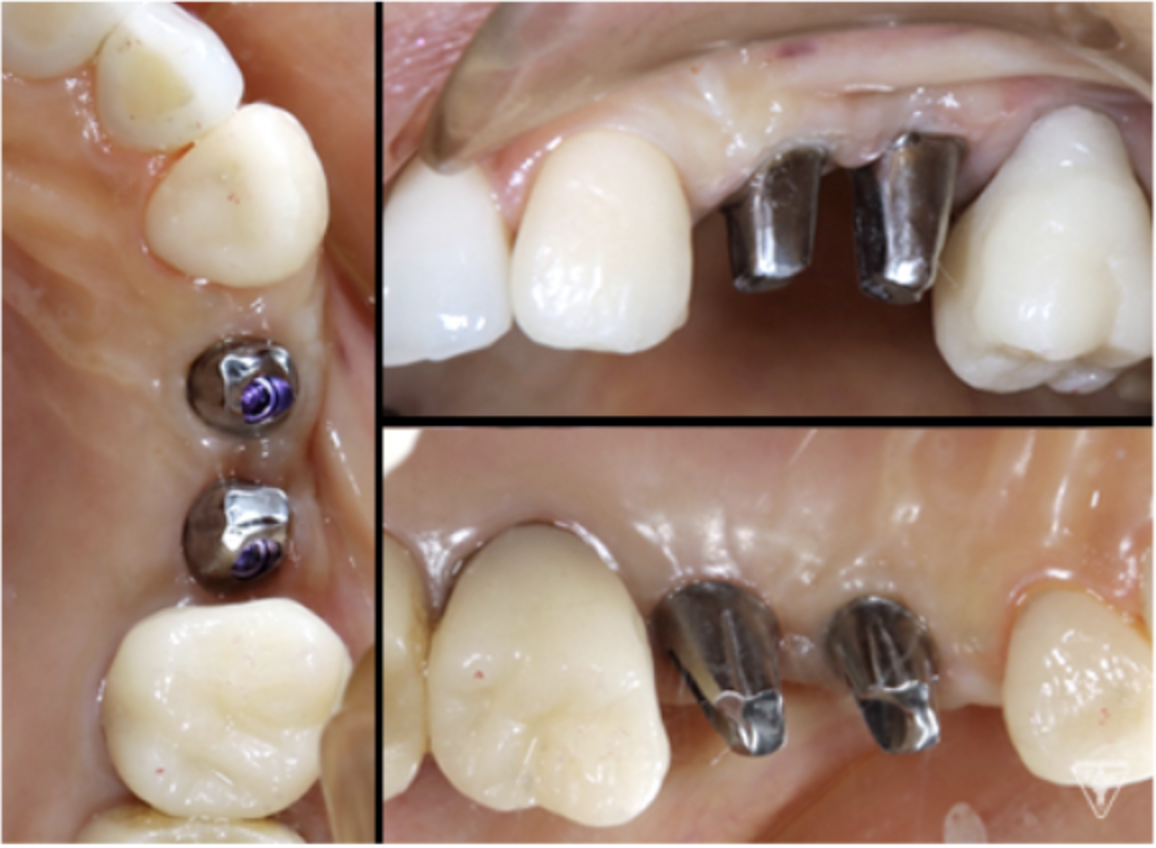

インプラント

最終補綴物装着時

咬合調整

粉砕効率の高い小さな点による均衝接触をつくります。

咬合様式は、ミューチャリープロテクトオクルージョンを付与しました。

咬合平面の評価(SHILLAⅡの平面板による)